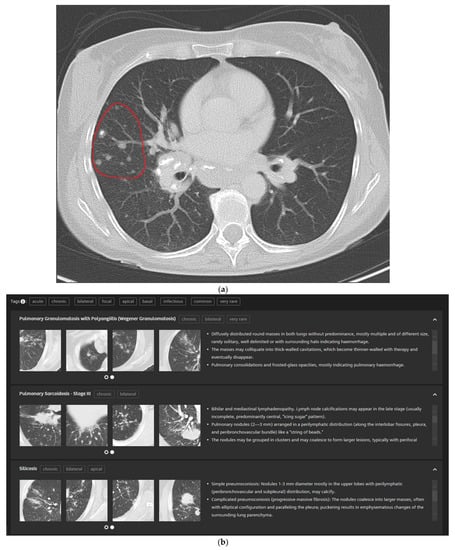

In detail, the participants drew a ROI into their perceived representative pattern in each case which was then analyzed by the CBIR (Figure 3a). The readers are then presented with the CBIR results (Figure 3b). To further improve the retrieval results the CBIR features the possibility to input clinical information in the form of high-level semantic features (e.g., smoking, infectious, chronic etc.) (Figure 3c).

Figure 3.

5 mm transversal lung window CT of a 51-year-old female patient with pulmonary sarcoidosis and corresponding CBIR user interface: Participants were shown the corresponding 5 mm transversal lung window CTs for each case. They then drew a ROI into the area with their supposed dominant pattern (a). Readers were then presented the CBIR results (b) and could select high-level semantic features (e.g., chronic, bilateral) to filter retrieval results (c).